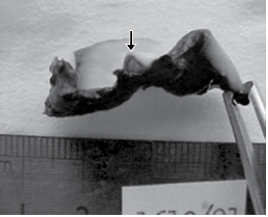

A figura seguinte refere-se à lesão encontrada na carótida comum de vítima de suicídio por enforcamento.

enunciado 723175-1

Observa-se, no terço médio, o destacamento da túnica externa das outras túnicas do vaso, que corresponde ao sinal de